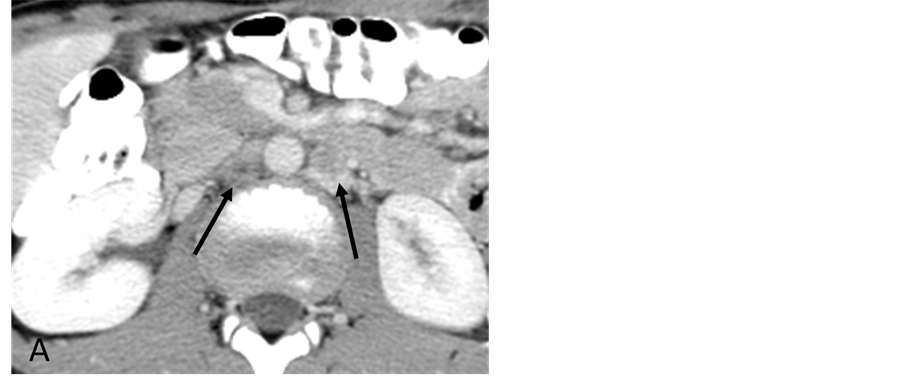

With the patient under general anesthesia, a 5-Fr Omni Flush catheter (Angio Dynamics, Queensbury, NY, USA) was placed in the aorta above the celiac axis from a percutaneous retrograde transfemoral arterial approach, and aortograms were performed, first with 30 cc of CO2 and then in the anterior-posterior (AP) and left anterior-oblique (LAO) projections with Visipaque (GE Healthcare, Cork, Ireland, UK). During each of the runs, there was a moderate increase in blood pressure from baseline systolic pressures of 120 s to 145 - 150 s, lasting 5 minutes, accompanied by bradycardia and transient arrhythmia. A nitroglycerin drip was started; however, the patient did not require any alpha or beta blockers. Next, a 5-Fr shepherd hook catheter (Angio Dynamics, Queensbury, NY, USA) was positioned and digital subtraction angiography (DSA) was performed, sequentially, in the right and left renal arteries, superior mesenteric artery, and finally the celiac axis. The aortograms revealed two vascular retroperitoneal tumors to the right and left of the aorta, at the level of L1-2, measuring 22 mm × 27 mm and 26 mm × 27 mm, respectively (Figure 2(A) and Figure 2(B)). The right retroperitoneal mass was located posteroinferior to the right renal artery and posterior to the inferior vena cava (IVC). The left retroperitoneal mass was located between the left main renal artery and the inferior accessory renal artery. The inferior accessory renal artery supplying the lower pole of left kidney showed diffuse narrowing due to either compression or catecholamine release by the tumor (Figure 3(A) and Figure 3(B)). Subsequently, bilateral renal arteriograms were performed without a hypertensive response to the injection of contrast material. The right main renal artery was displaced by the tumor with mild arterial narrowing (Figure 4(A) and Figure 4(B)). Left renal arteriogram showed a patent main renal artery with a circumaortic renal vein (Figure 5(A) and Figure 5(B)).

Figure 2. (A) CO2 digital subtraction aortogram, arterial phase, showing hypervascular retroperitoneal tumors (arrows) (B) late arterial phase. There is increased CO2 accumulation throughout the tumors (arrows).